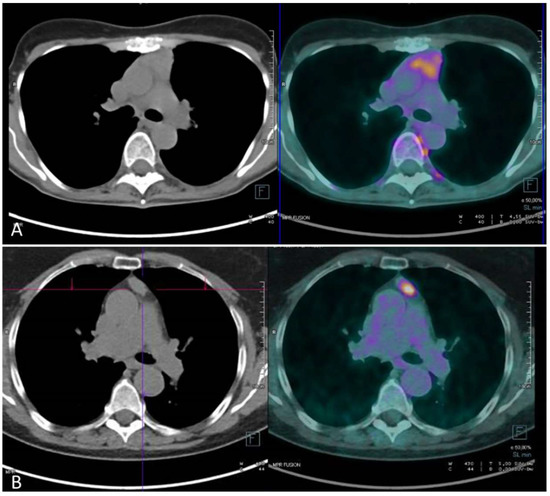

2.4. PET/CT to Predict Pathological Response after Induction Therapy

The Knowledge of Pathologic Response Is Still Limited, but PET/CT Showed Interesting and Promising Results in This Field